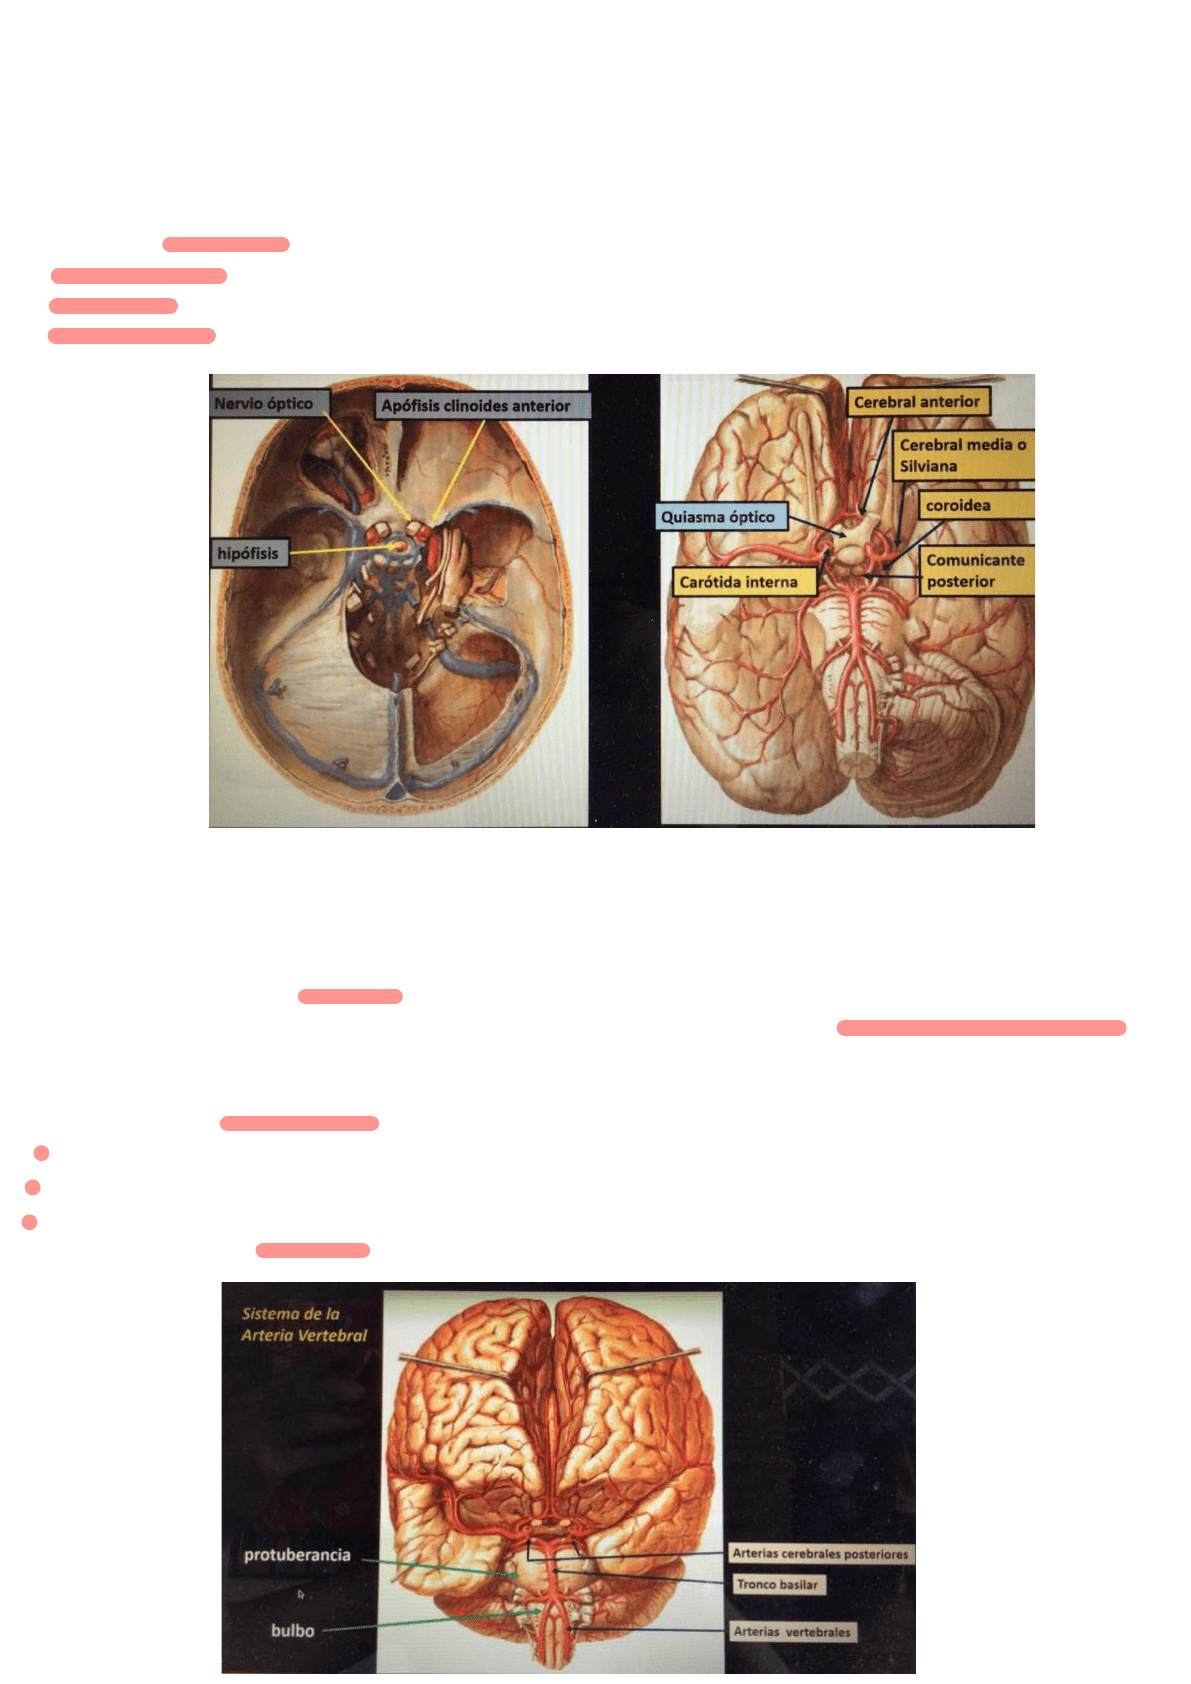

Sistema de la carótida interna

Emerge lateralmente a la pared del seno cavernoso y por dentro de la apófisis clinoides anterior.

Pasa lateral-externo al nervio óptico.

Luego de un recorrido, envía una rama, la arteria oftálmica

Luego se divide en sus cuatro ramas terminales:

La primera es la cerebral anterior: que se dirige hacia adelante

Cerebral media/silviana: que se dirige a la cisura de Silvio

Coroidea anterior: se dirige hacia atrás

Comunicante posterior: se dirige a la base del cerebro y forma uno de los lados del polígono de Willis

Sistema de la arteria vertebral

Entra por el agujero occipital y contornea el tronco del encéfalo situados a los lados del bulbo.

Convergen hacia arriba y forman el tronco basilar en la protuberancia

Llegando al borde superior de la protuberancia y en el espacio perforado posterior se divide en sus dos ramas: arterias cerebrales derecha e izquierda.

Antes de dar esas ramas dan muchas ramas colaterales para el bulbo, la protuberancia, los pedúnculos y el cerebelo. Son tres para cada uno.